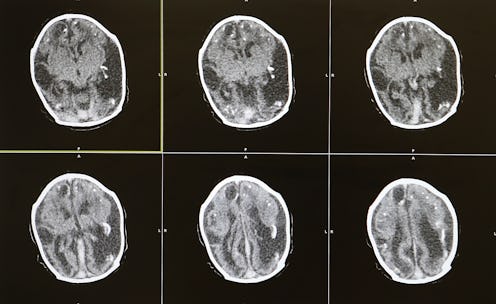

Scientists believe this compulsive behavior can be traced back to one cell: the fast spiking interneuron (FSI for short). According to the study, the striatum “contains two sets of neural pathways: a ‘go’ pathway, which incites an action, and a ‘stop’ pathway, which inhibits action.” Scientists found mice driven by compulsive and obsessive behavior, such as pushing the lever, exhibited much higher levels of activity from FSIs. Though FSIs make up only 1 percent of the cells in the striatum, they extremely powerful. FSI cells look like jellyfish tendrils, and though rare, they connect to at least 95 percent of the start and stop pathways the study researched.